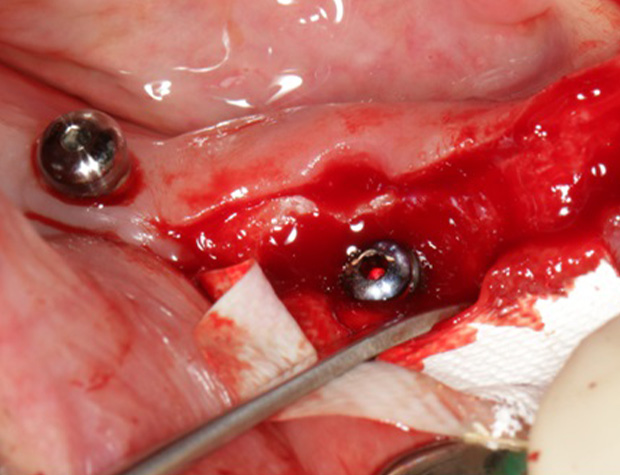

Implantologische Fälle schnell und einfach lösen ist der Wunsch eines jeden Implantologen. Die Realität ist allerdings eine andere. Diverse Knochendefekte, schlechte Knochenqualität, Weichgewebsdefizite und viele weitere schlechte Grundvorraussetzungen existieren und machen jeden Eingriff zu einer Herausforderung. Um solche implantologischen Fälle dennoch erfolgreich zu therapieren, benötigen Sie einfach handhabbare Techniken, die schnell zu erlernen sind und nahezu jeden Fall realisierbarer gestalten kann. Die Osseodensifikation ist eine Technik die schnell und einfach zu erlernen ist und viele Möglichkeiten Ihnen bietet. Das Implantatbett bei schlechter Knochenqualität optimal aufbereiten ist bereits bekannt, aber einen Kieferkamm spreizen oder sogar einen Sinuslift vorhersagbar durchzuführen, ohne die Schneider’sche Membran zu perforieren, das sind die Optionen, die Sie schnell und einfach erlernen können. Um Ihr Portfolio noch zu erweitern, wird die GBR-Technik mittels moderner Materialien Ihnen beigebracht.